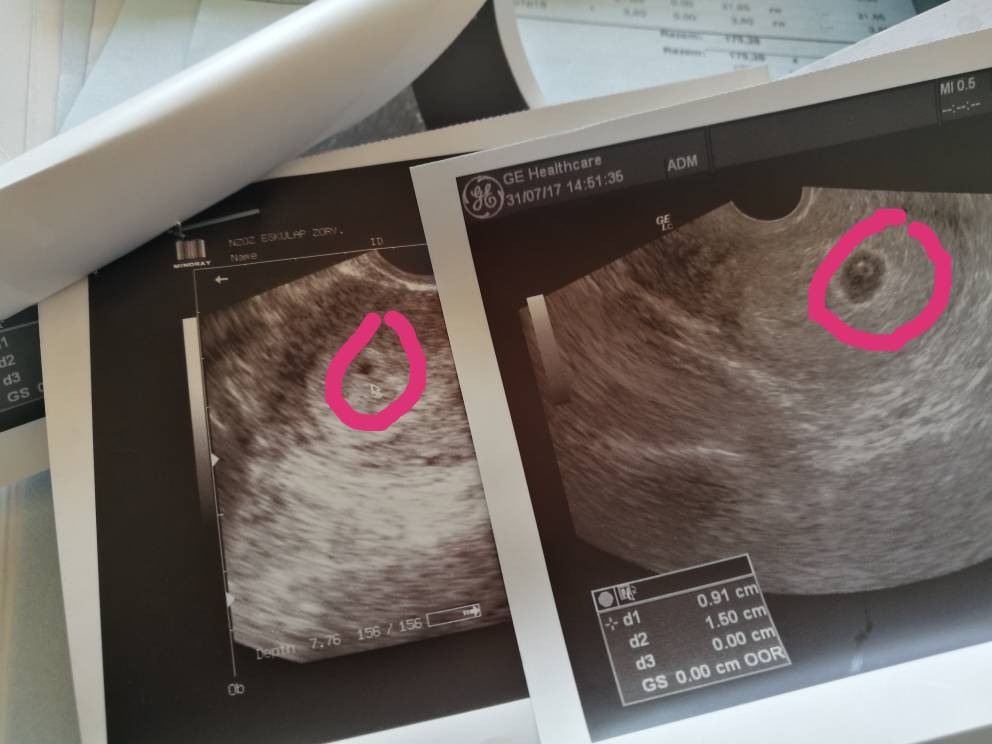

Tutaj jest pierwsze zdjęcie mojej Anny [emoji3526]

IMG_20170731_194518.jpeg

• IMG_20170731_194518.jpeg